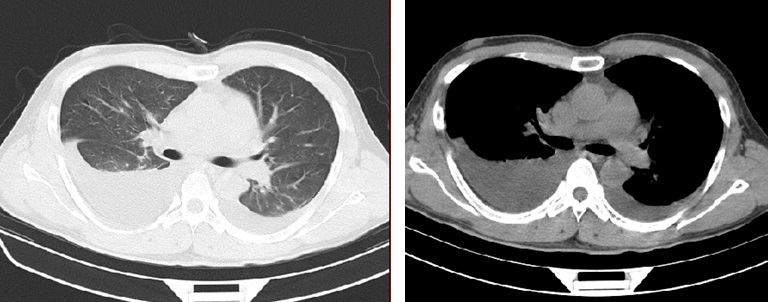

胸腔积液CT图片

胸腔积液CT图片,

患者胸部ct及胸片检查右侧胸腔积液.

胸部ct示双侧胸腔积液并

图4 胸部ct,提示肺部感染合并少量胸腔积液.

2患者胸部ct示双肺新发磨玻璃渗出影(黑色箭头;双侧胸腔积液较前